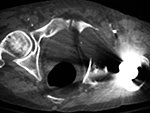

Particle disease (arrows) left hip coronal CT image |

68 year-old man with particle disease from a worn out left hip prosthesis. Bony destruction (arrows) is in the left supra-acetabular region and in the left greater trochanter with a pathologic fracture. |

|